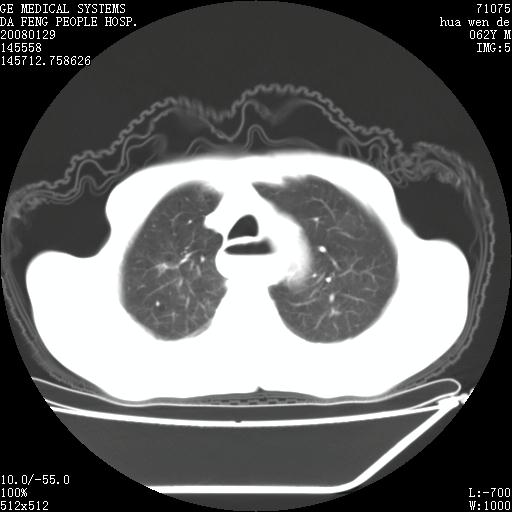

男性,67岁。作肺部检查时发现

1.整个食管扩张,未见明显占位性病变,贲门区亦未见明显占位病变,考虑:贲门失驰缓症;

2.右上肺病变边缘可见毛刺,囊壁厚度不均匀,周围境界较清楚,未见炎性渗出性影,右上肺外带可见片状影,边缘不清,考虑:肺癌伴空洞形成、右上肺炎。

食管全程扩张,壁均匀不厚,喷门失弛缓症

右上肺空洞可见液平,临近肺野磨玻璃密度,考虑1.结核2.脓肿

右上肺空洞可见液平,临近肺野磨玻璃密度,考虑1.结核2.脓肿 支持!